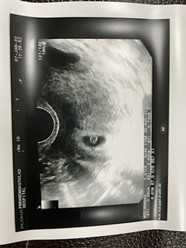

แม่ๆ ทีมสิงหา65 ไปถึงไหนกันบ้างแล้วคะ แพ้กันบ้างมั้ย บ้านนี้ ท้อง2โชคดีมาก ไม่ค่อยแพ้เลย ตอนนี้9w4d ท้องออกแล้ว กำหนด 30สิงหา

สิงหาค่ะ ตอนนี้ 24w6d ท้องแรกค่า 🥰

บ้านนี้30สิงหาจ้ะตอนนี้24wแล้ว